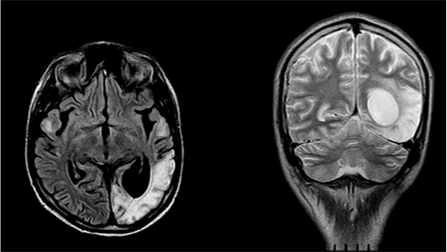

The patient's condition worsened, there were attacks of the type of right-sided hemiconvulsions, episodes of visual impairment lasting from 1 to 5hours, simple visual hallucinations, stopped by intramuscular administration of diazepam (Figure 3) were observed. Since February 2010, he received valproic acid 1500mg/day, ¾ pagluferal tablets.

Figure 3 MRI of the brain in FLAIR and T2 VI modes (February 2011). There is a focus of increased signal intensity in the cortico-subcortical regions of the left occipital lobe.